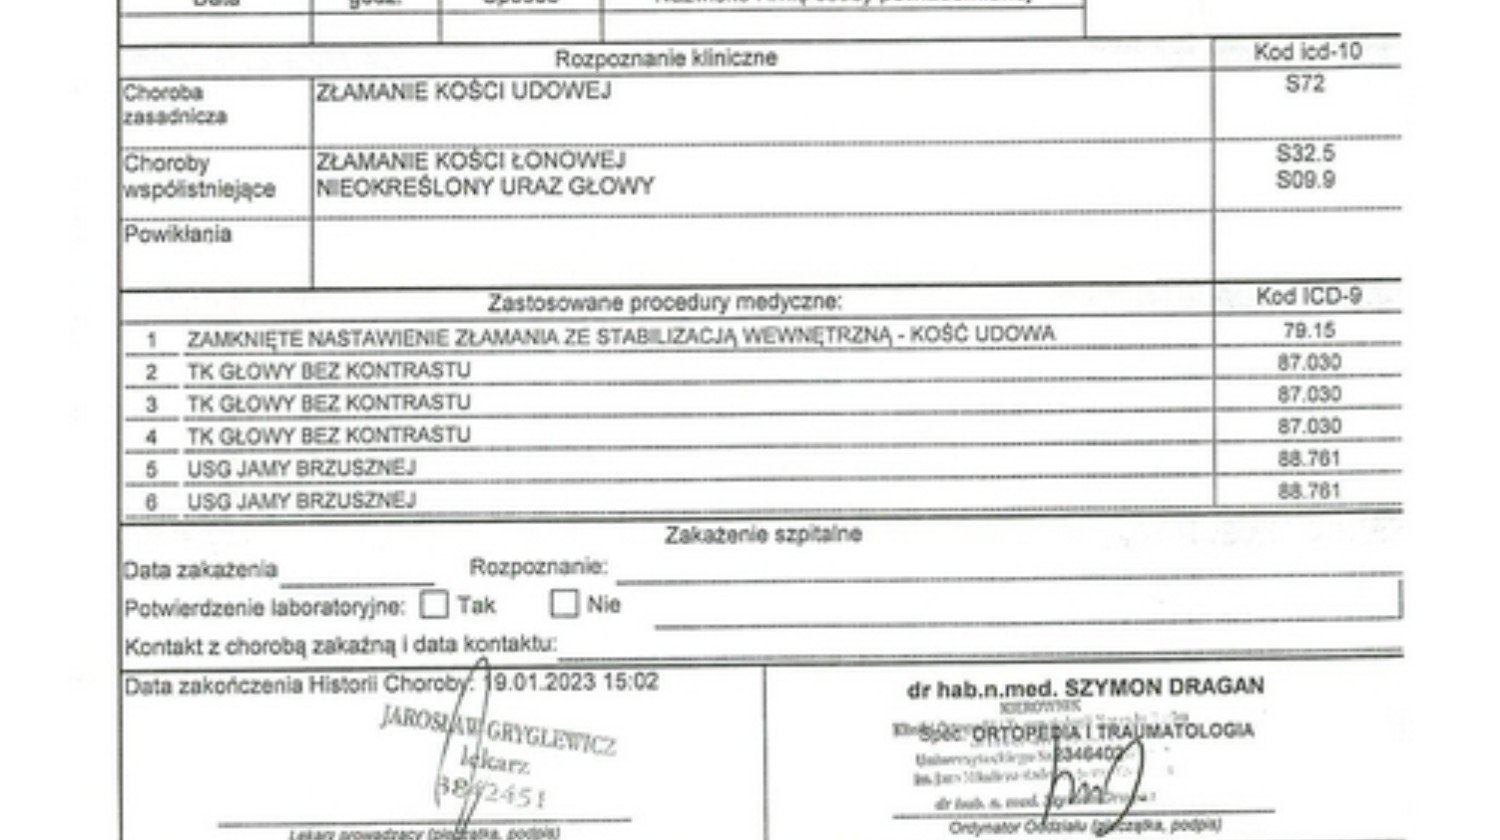

Wyrok sądu: „w dniu 4 stycznia 2023 r. w miejscowości Spalice na ul. Wrocławskiej, powiat oleśnicki, (...) nieumyślnie naruszył zasady bezpieczeństwa w ruchu lądowym i spowodował wypadek drogowy w ten sposób, że kierując samochodem osobowym marki Citroen (…) wbrew zasadom bezpieczeństwa ruchu, zbliżając się do wyznaczonego przejścia dla pieszych nie zachował zasad szczególnej ostrożności, właściwej obserwacji przedpola jazdy, przez co pozbawiał się możliwości uniknięcia wypadku, doprowadzając do potrącenia pieszego Rafała Walendowskiego przechodzącego przez wyznaczone przejście dla pieszych, w następstwie czego pokrzywdzony doznał obrażeń ciała w postaci złamania kości ciemieniowej prawej, złamania kości skroniowej prawej, złamania trzonu kości klinowej, złamania łuku kości jarzmowej prawej, złamania ściany przedniej i tylno-bocznej zatoki szczękowej prawej, podbiegnięcia krwawego w okolicy oczodołowej prawej, ogniska tłuczenia mózgu w płacie skroniowym prawym i lewym oraz w śródmózgowiu z ich wtórnym ukrwotocznieniem, krwiaka przymózgowego nad prawą półkulą mózgu, złamania kości łonowej bez przemieszczenia, złamania szyjki kości udowej prawej, które stanowią uszczerbek na zdrowiu i powodują naruszenie czynności ciała i rozstrój zdrowia na czas dłuższy niż 7 dni tj. o czyn z art. 177 § 1 k.k."

Minęły ponad 2 lata od wypadku. Orzeczenie lekarza orzecznika ZUS z dnia 07.02.2025 r. - niezdolny do pracy na kolejne 6 miesięcy. Mogę prawie normalnie chodzić (nadal trwa rehabilitacja) i żyć. Jeszcze leczę moją potłuczoną głowę (wielkie podziękowania dla Uniwersyteckiego Szpitala Klinicznego im. Jana Mikulicza-Radeckiego we Wrocławiu - "cudotwórcy"; byłem tam 15 dni), dłużej dają znać o sobie powikłania po obrażeniach głowy - leczę się psychiatrycznie. Po wypadku zlikwidowałem działalność (dawałem pracę 19 osobom), pozostały długi finansowe, nie miałem jak zarabiać na koszty, kredyty (ok. 120 tys.) które z czasem są coraz większe (żaden ze klepów nie był moją własnością). Chciałbym znowu spróbować własnych sił z działalnością, jednak zaległości w opłatach i spłatach uniemożliwiają mi zdobycie własnych (pożyczonych) środków finansowych. Bardzo chciałbym znowuż wrócić do aktywności zawodowej jako przedsiębiorca. Mając własną działalność pomagałem ludziom potrzebującym pomocy - ile tylko mogłem. Teraz sam potrzebuję pomocy. Liczę na dobroć serc ludzkich. Za każdą wpłatę bardzo dziękuję.